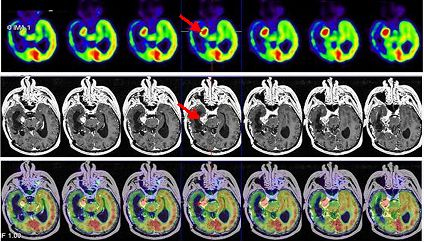

A los 3 meses, el paciente refiere persistencia de la cefalea, anestesia de hemifacies derecha, empeoramiento de hemianopsia izquierda y alteración de la marcha por hemiparesia izquierda. La RNM informa disminución de volumen de la lesión metastásica en tentorio y adyacente a vermis cerebeloso. La infiltración tumoral mesial temporal derecha ha disminuido de tamaño y la de ubicación más posterior también ha decrecido, con componente hemorrágico en su interior. Se realiza estudio PET-RNM de reestadificación (figs. 3 y 4).